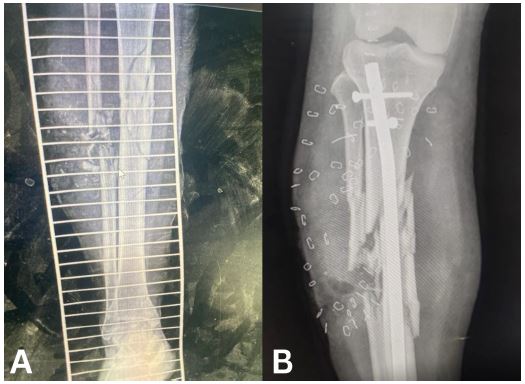

Case 7

A 26-year-old female presented with a Gustilo-Anderson Grade II open fracture of the right femur. She underwent external fixation for 10 weeks. IV Ceftriaxone antibiotics were given for 48 hours before removal of the external fixator. The fracture subsequently underwent closed reduction and fixation with a retrograde nail and the pin site underwent debridement. The wounds healed by week 4 and the patient was started on full weight-bearing 2 days after fixation with the nail.

Figure 7: (A) Radiograph of external fixator. (B) External fixator and wound at week 3.